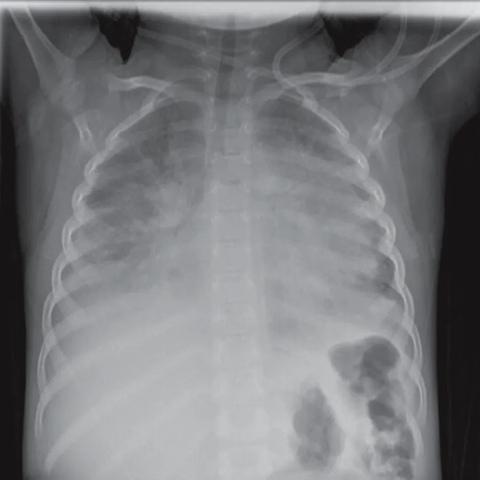

22岁日本写真偶像丰岛心樱在社交平台发布的胸腔X光片,本是普通体检记录,却因清晰呈现的骨骼与软组织轮廓,意外成为舆论焦点,网友讨论的核心并非肺部健康指标,而是“肋骨间距的标准度”“锁骨线条的艺术感”,相关话题阅读量在24小时内突破10亿次,远超对体检结果的关注,这一现象折射出:当偶像的身体影像脱离医疗语境,公众注意力会如何从健康关切转向审美评判?

• 社交平台的“二次创作”助推:网友截取X光片中的锁骨与肋骨轮廓,配文“这才是人体美学教科书”等文案,在社交媒体形成二次传播,话题标签#丰岛心樱的骨骼美学#阅读量超8亿;